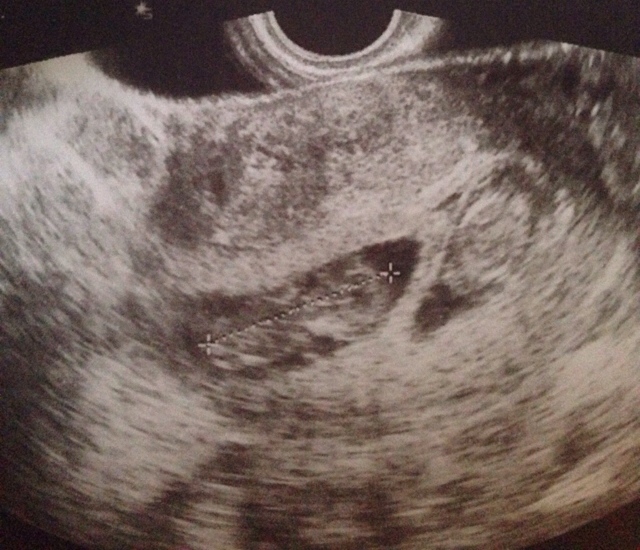

due cuoricini per i due fagiolini.